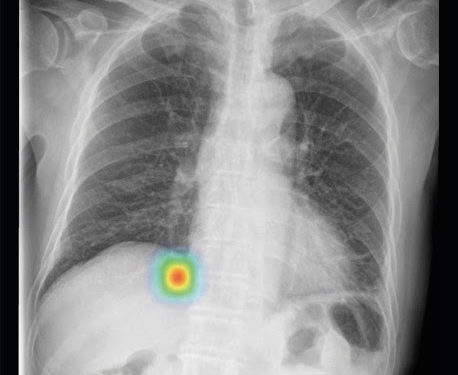

Программное обеспечение Lunit INSIGHT CXR предназначено для обеспечения точного и мгновенного анализа рентгеновских снимков грудной клетки путем картирования местоположения проблемных мест и отображения оценочного расчета их фактической сущности. Оно точно определяет 10 наиболее распространенных результатов рентгенографии грудной клетки, расставляет приоритеты для случаев с аномалиями, тем самым позволяя быстро сортировать обычные случаи и давая возможность рентгенологам сосредоточиться на расшифровке аномальных случаев. Алгоритм работает с точностью 97-99%, его производительность подтверждена в публикациях в таких солидных журналах, как Radiology, JAMA Network Open и др.